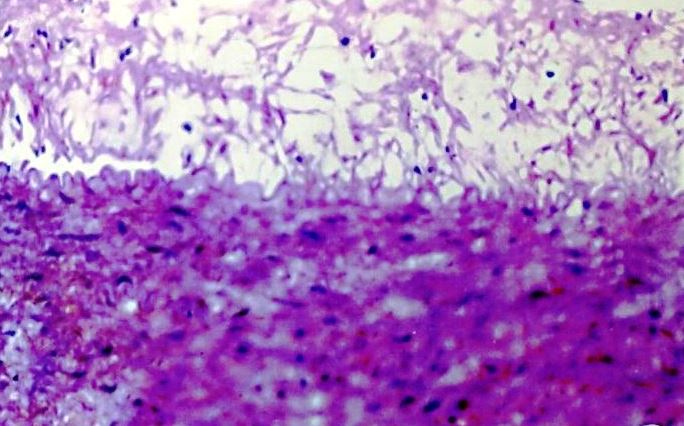

The histopathological examinations were also performed in the ascending aorta and coronary artery in high cholesterol animal diet group and high cholesterol animal diet accompanied with C. verum extract group when compared with control (fig. 3-10).

Asending Aorta

Histological study showed that control group had completely normal arteries without any lesion in intima or media. In our study athero fed rabbits showed well developed atheromatous plaque protruding in to the lumen of the aorta. There were many foamy (lipid-laden) macrophages and dense fibrous tissue layer in the plaque could be seen. Media was also showing foam cell. The animals consuming the C. verum along with high cholesterol, the severity of lesions were significantly reduced, three layers of aortic wall were distinct, and only few lipid-laden cells were present in the medial layer when compared with the rabbits consuming the high cholesterol diet (group II) (fig. 3-6).

Fig. 3: Ascending aorta of control rabbit

Fig. 4: Ascending aorta of rabbit after Athero diet feeding for 120 d

Fig. 5: Ascending aorta of rabbit-Athero Diet+C. verum 200 mg concurrent (120 d)

Fig. 6: Ascending aorta of rabbit-Athero Diet+C. verum 300 mg concurrent (120 d)